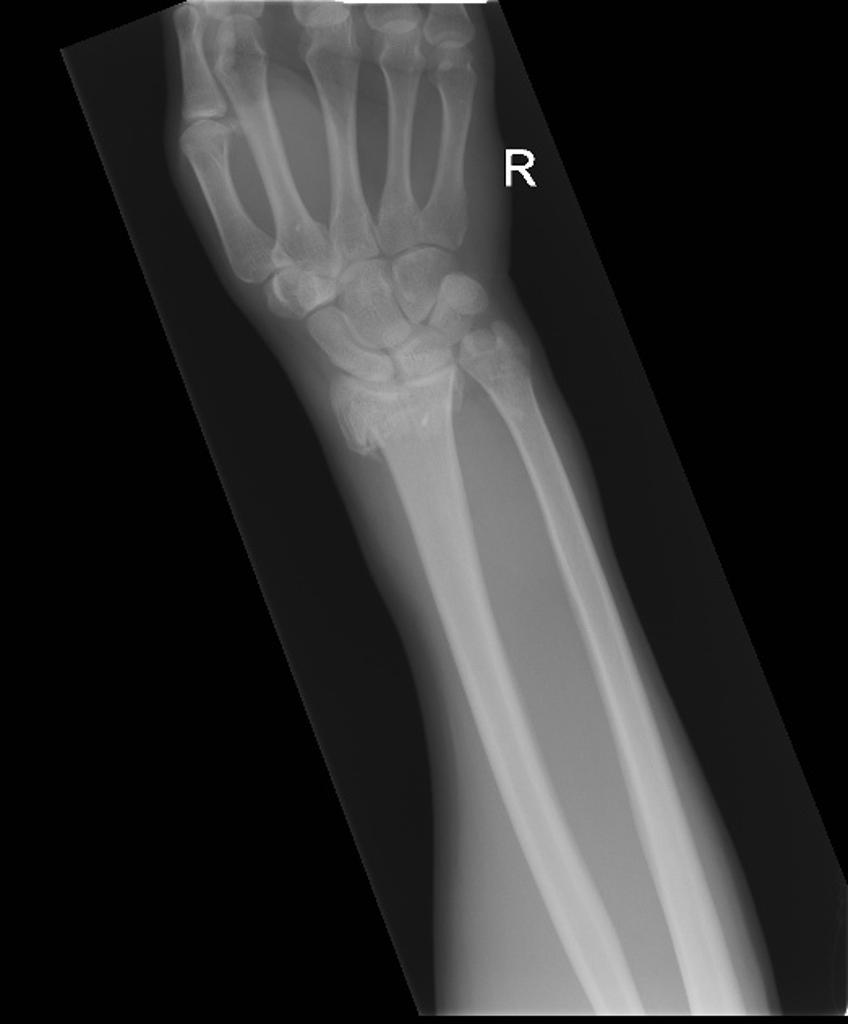

Patient presents to A+E with a broken arm. On examination, the affected arm shows palmar (volar) deviation of the distal radius. They state that they fell backwards after slipping and their hands got caught under them. What is the likely diagnosis?

Smith’s fracture

Volar displacement of distal radius

‘garden spade’ deformity